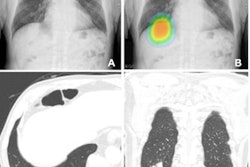

- It can be used to analyze images across a range of modalities: x-ray, CT, ultrasound, and MRI.

- It can identify, localize, and classify conditions such as pulmonary nodules and breast lesions.